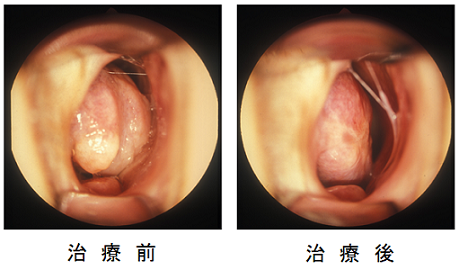

- アレルギー性鼻炎に対するレーザー治療

鼻の中に麻酔液を染み込ませたガーゼを30分間入れた後に3~4分間照射します。 痛みはありません。年中児から治療が可能です。内服薬の服用を約半分に減らせ、効果が数年持続します。 鼻中隔湾曲症では効果は限定的です。

鼻の中に麻酔液を染み込ませたガーゼを30分間入れた後に3~4分間照射します。 痛みはありません。年中児から治療が可能です。内服薬の服用を約半分に減らせ、効果が数年持続します。 鼻中隔湾曲症では効果は限定的です。- レーザー治療前後の鼻腔内所見